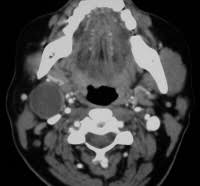

Normally, when i'm on a hunting expedition, (no clue), i would order a ct scan then further imaging as warranted. Note that with some conditions (like suspected gallbladder issues) ultrasound imaging may be the preferred choice. The differential diagnosis for abdominal pain is broad, encompassing gastrointestinal, gynecologic, urologic, vascular, and musculoskeletal conditions. Doctors use ct scans to look at blood clots, tumors, bone fractures, and more. It may be used with or without a contrast dye to see internal structures more clearly.

Ct scans of the abdomen may also be used to visualize placement of needles during biopsies of abdominal organs or tumors or during aspiration (withdrawal) of fluid from the abdomen. There are certain advantages of ct scan like we can make out bony structures better than mri. And the scans i had did not accurately show the soft tissue damage. A ct scan (or cat scan) is best suited for viewing bone injuries, diagnosing lung and chest problems, and detecting cancers. Recently had another mri for another health issue and as a side note when they read the scans they looked at studies suggest that routine imaging for low back pain is a waste of time and money that sometimes harms patients. .into my abdomnal pain i have been refered for a ct scan but can't understand why its not an mri scan insteadi thought mri was much safer than ct as there is mris could be, without letting me decide for myself if i wanted one anyway.i finally was able to get an abdominal and pelvic mri from a sympathetic chiropractor. Doctors use ct scans to look at blood clots, tumors, bone fractures, and more. During a ct scan, a person lies down in a large.

A ct scan (or cat scan) is best suited for viewing bone injuries, diagnosing lung and chest problems, and detecting cancers. The differential diagnosis for abdominal pain is broad, encompassing gastrointestinal, gynecologic, urologic, vascular, and musculoskeletal conditions. The abdomen and pelvis can both be scanned together in one shot with. Learn the similarities and differences in the two scans and how you can prepare abdominal abnormalities: Doctors use ct scans to look at blood clots, tumors, bone fractures, and more. What if the patient in the er insists on an mri to for this reason, wait time and scan times for mri are much longer than ct. We explain the details and differences between ct scans and mris, and help you weigh the benefits and risks of. The person lies on a table that moves through a scanning for mri, people who have trouble with claustrophobia or are unable to hold their breath, which may be required for certain abdominal imaging tests, may not. Like the other 3 tests in this group, the ct scan is painless. Since there is a range of causes for abdominal pain. There are certain advantages of ct scan like we can make out bony structures better than mri. Ct scans of the abdomen may also be used to visualize placement of needles during biopsies of abdominal organs or tumors or during aspiration (withdrawal) of fluid from the abdomen. Why would your doctor recommend one over the other?

Unknown masses in the liver, pancreas or kidneys can be identified as tumors or not. Like the other 3 tests in this group, the ct scan is painless. A ct takes, on average, less than 60 seconds while an abdominal mri takes closer to 30 minutes. Abdomen pain and suspicion, should i get a ct scan or mri? answered by a verified doctor: A general surgeon does not necessarily mean you need surgery, but their training makes them experts in abd pains. Cat scans, mri scans, ultrasound, and mibg are shown and described. An mri is suited for examining soft tissue in ligament and tendon injuries, spinal cord injuries, brain tumors, etc. Pet scans provide metabolic information and are increasingly read alongside ct or mri (magnetic resonance imaging) scans, which provide anatomic information.